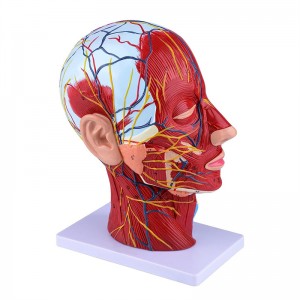

| Caracteristici | Modelul arată morfologia locală a laturilor interioare și exterioare ale secțiunii sagitale mediane a capului și a gâtului, precum și a structurilor vaselor de sânge și a nervilor și există 84 de părți care indică semne în total. |

【Model de mușchi neurovascular superficial】 extrem de detaliat, numere marcate, detașabile, adânciți înțelegerea mușchilor superficiali, vaselor, nervilor și structurilor interne ale capului și gâtului. Red-Artery, vene albastru, galben-port.

【Caracteristici】 arată mușchii superficiali ai feței expuse; vasele de sânge superficiale și nervii feței & scalp; structurile interioare ale glandei parotide și ale tractului respirator superior; Structura de secțiune sagitală a coloanei vertebrale cervicale.

Acest model arată detalii despre gâtul dreptului drept și secțiunea sagitală mijlocie a omului. inclusiv superficialul

mușchii feței expuse; vasele de sânge superficiale și nervii feței și ale scalpului; Structurile interioare

a glandei parotide și a tractului respirator superior; Structura de secțiune sagitală a coloanei vertebrale cervicale.

Modelul a arătat morfologia locală a secțiunilor sagitale mediale și laterale ale capului și gâtului și ale structurilor sale vasculare și nervoase, cu un total de 100 de indicatori de sit.

Acest model este un model natural de mușchi neurovascular superficial al capului și gâtului, 1 componentă, care arată detaliile capului drept și gâtului drept și secțiunea sagitală mediană, inclusiv mușchii superficiali expuși ai feței, vasele superficiale ale feței și scalpului, nervii și structura medială a glandei parotide și a tractului respirator superior și a structurii secțiunii sagitale a coloanei vertebrale cervicale